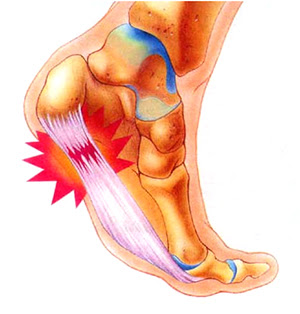

통증이 발생하는 이유는 족저 근막이 과도하게 늘어나거나 손상되기 때문입니다. 족저 근막은 발의 아치를 지탱하는 역할을 하며, 이곳에 지나치게 많은 압력이 가해지면 염증이 발생하게 됩니다. 통증이 지속되는 경우, 걷기나 서 있는 것만으로도 불편함을 느낄 수 있습니다.

네 번째로 통증이 특정 위치에서 집중적으로 느껴지는 증상이 있습니다. 대개 발바닥 중앙, 특히 아치 부분이 가장 아픈 곳입니다. 그러나 개인차가 있을 수 있으며, 종종 발꿈치 쪽이나 발목으로 방사되는 통증을 경험하는 경우도 많습니다.